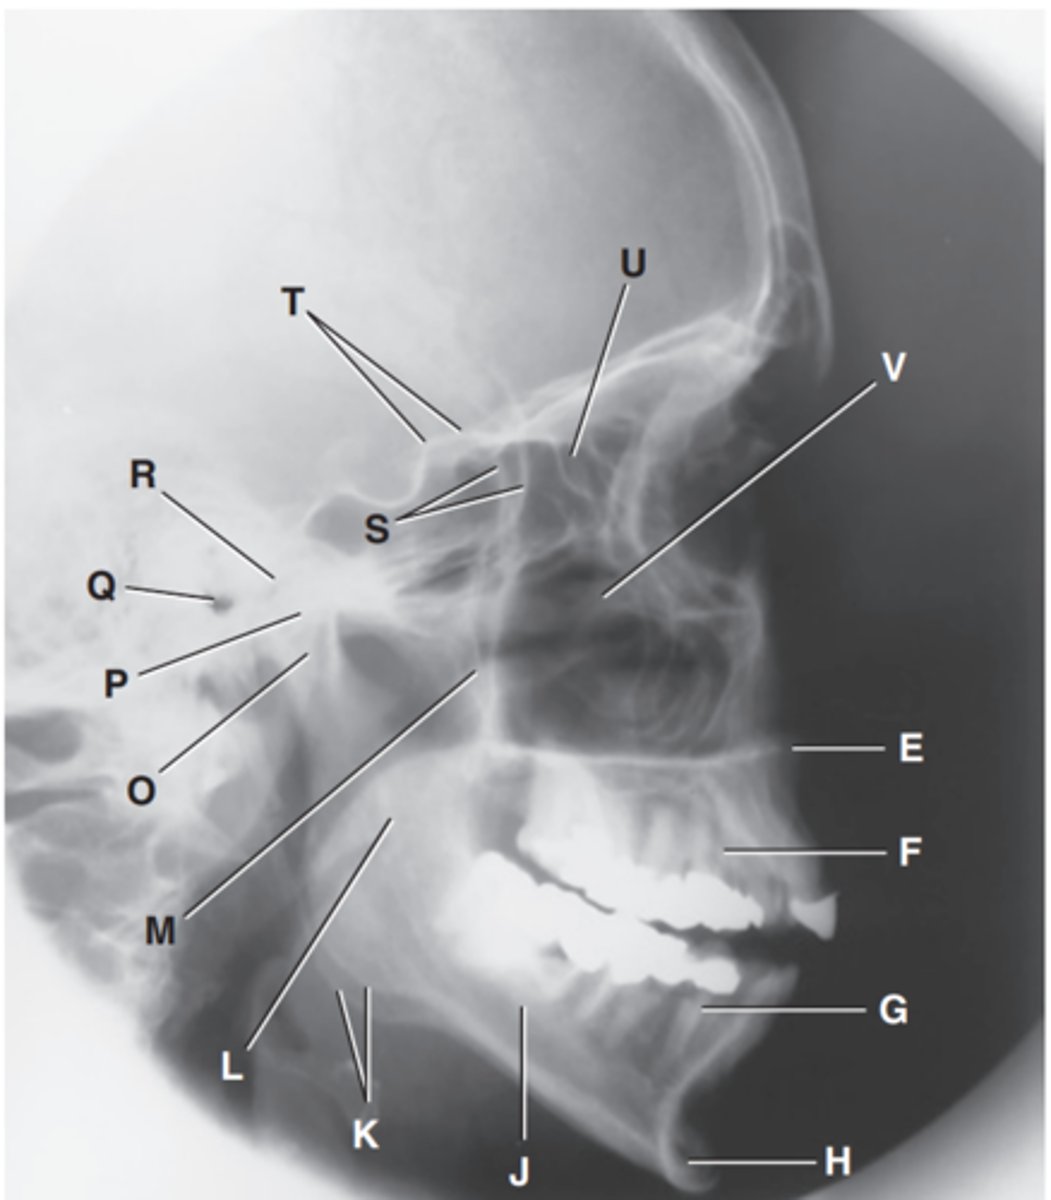

Zygomatic arch

Label A

Right zygomatic bone

Label B

Right nasal bone

Label C

Frontal process of right maxilla

Label D

Anterior nasal spine

Label E

Alveolar process of maxilla

Label F

Alveolar process of mandible

Label G

Mentum or mental protuberance

Label H

Mental foramen

Label I

Body of mandible

Label J

Angle (gonion)

Label K

Ramus of mandible

Label L

Coronoid process

Label M

Mandibular notch

Label N

Neck of mandibular condyle

Label o

Condyle or head of mandible

Label P

EAM

Label Q

TM fossa of temporal bone

Label R

Greater wings of sphenoid

Label S

Lesser wings of sphenoid with anterior clinoid processes

Label T

Ethmoid sinuses between orbits

Label U

Body of maxilla containing maxillary sunuses

Label V